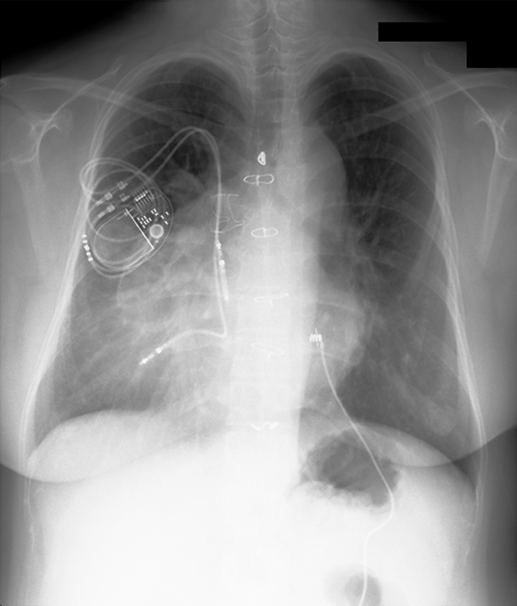

胸部X線写真(Fig. 1)

Fig. 1 Preoperative chest X-ray shows dextrocardia, the cardio-thoracic ration of 60%. Mild lung congestion is noted in both lungs. Permanent pacemaker is implanted below the right clavicle with two leads placed into the right atrium and the apex of the left ventricle

心胸郭比60%,肺血管陰影増強なし,左第3, 4弓突出あり.